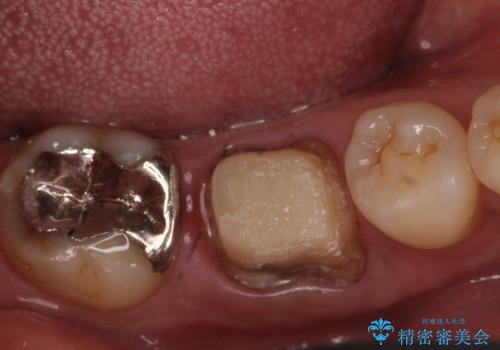

- 数年前から歯茎から膿が出る、治療してもよくならないので診て欲しいといらっしゃった方の症例です。

再根管治療を行い膿の出口の消失及び根尖病変の縮小を確認後、オールセラミッククラウンによる補綴を行いました。

今回用いたオールセラミッククラウンはジルコニアフレームという白い素材の上にセラミックを盛っているため、審美性が非常に高いのが特徴です。

また、ジルコニアは人工ダイヤモンドの材料にも使われているほど高い強度を持っており、そのためオールセラミッククラウンは審美性だけでなく、奥歯やブリッジの補綴も可能とするクラウンです。